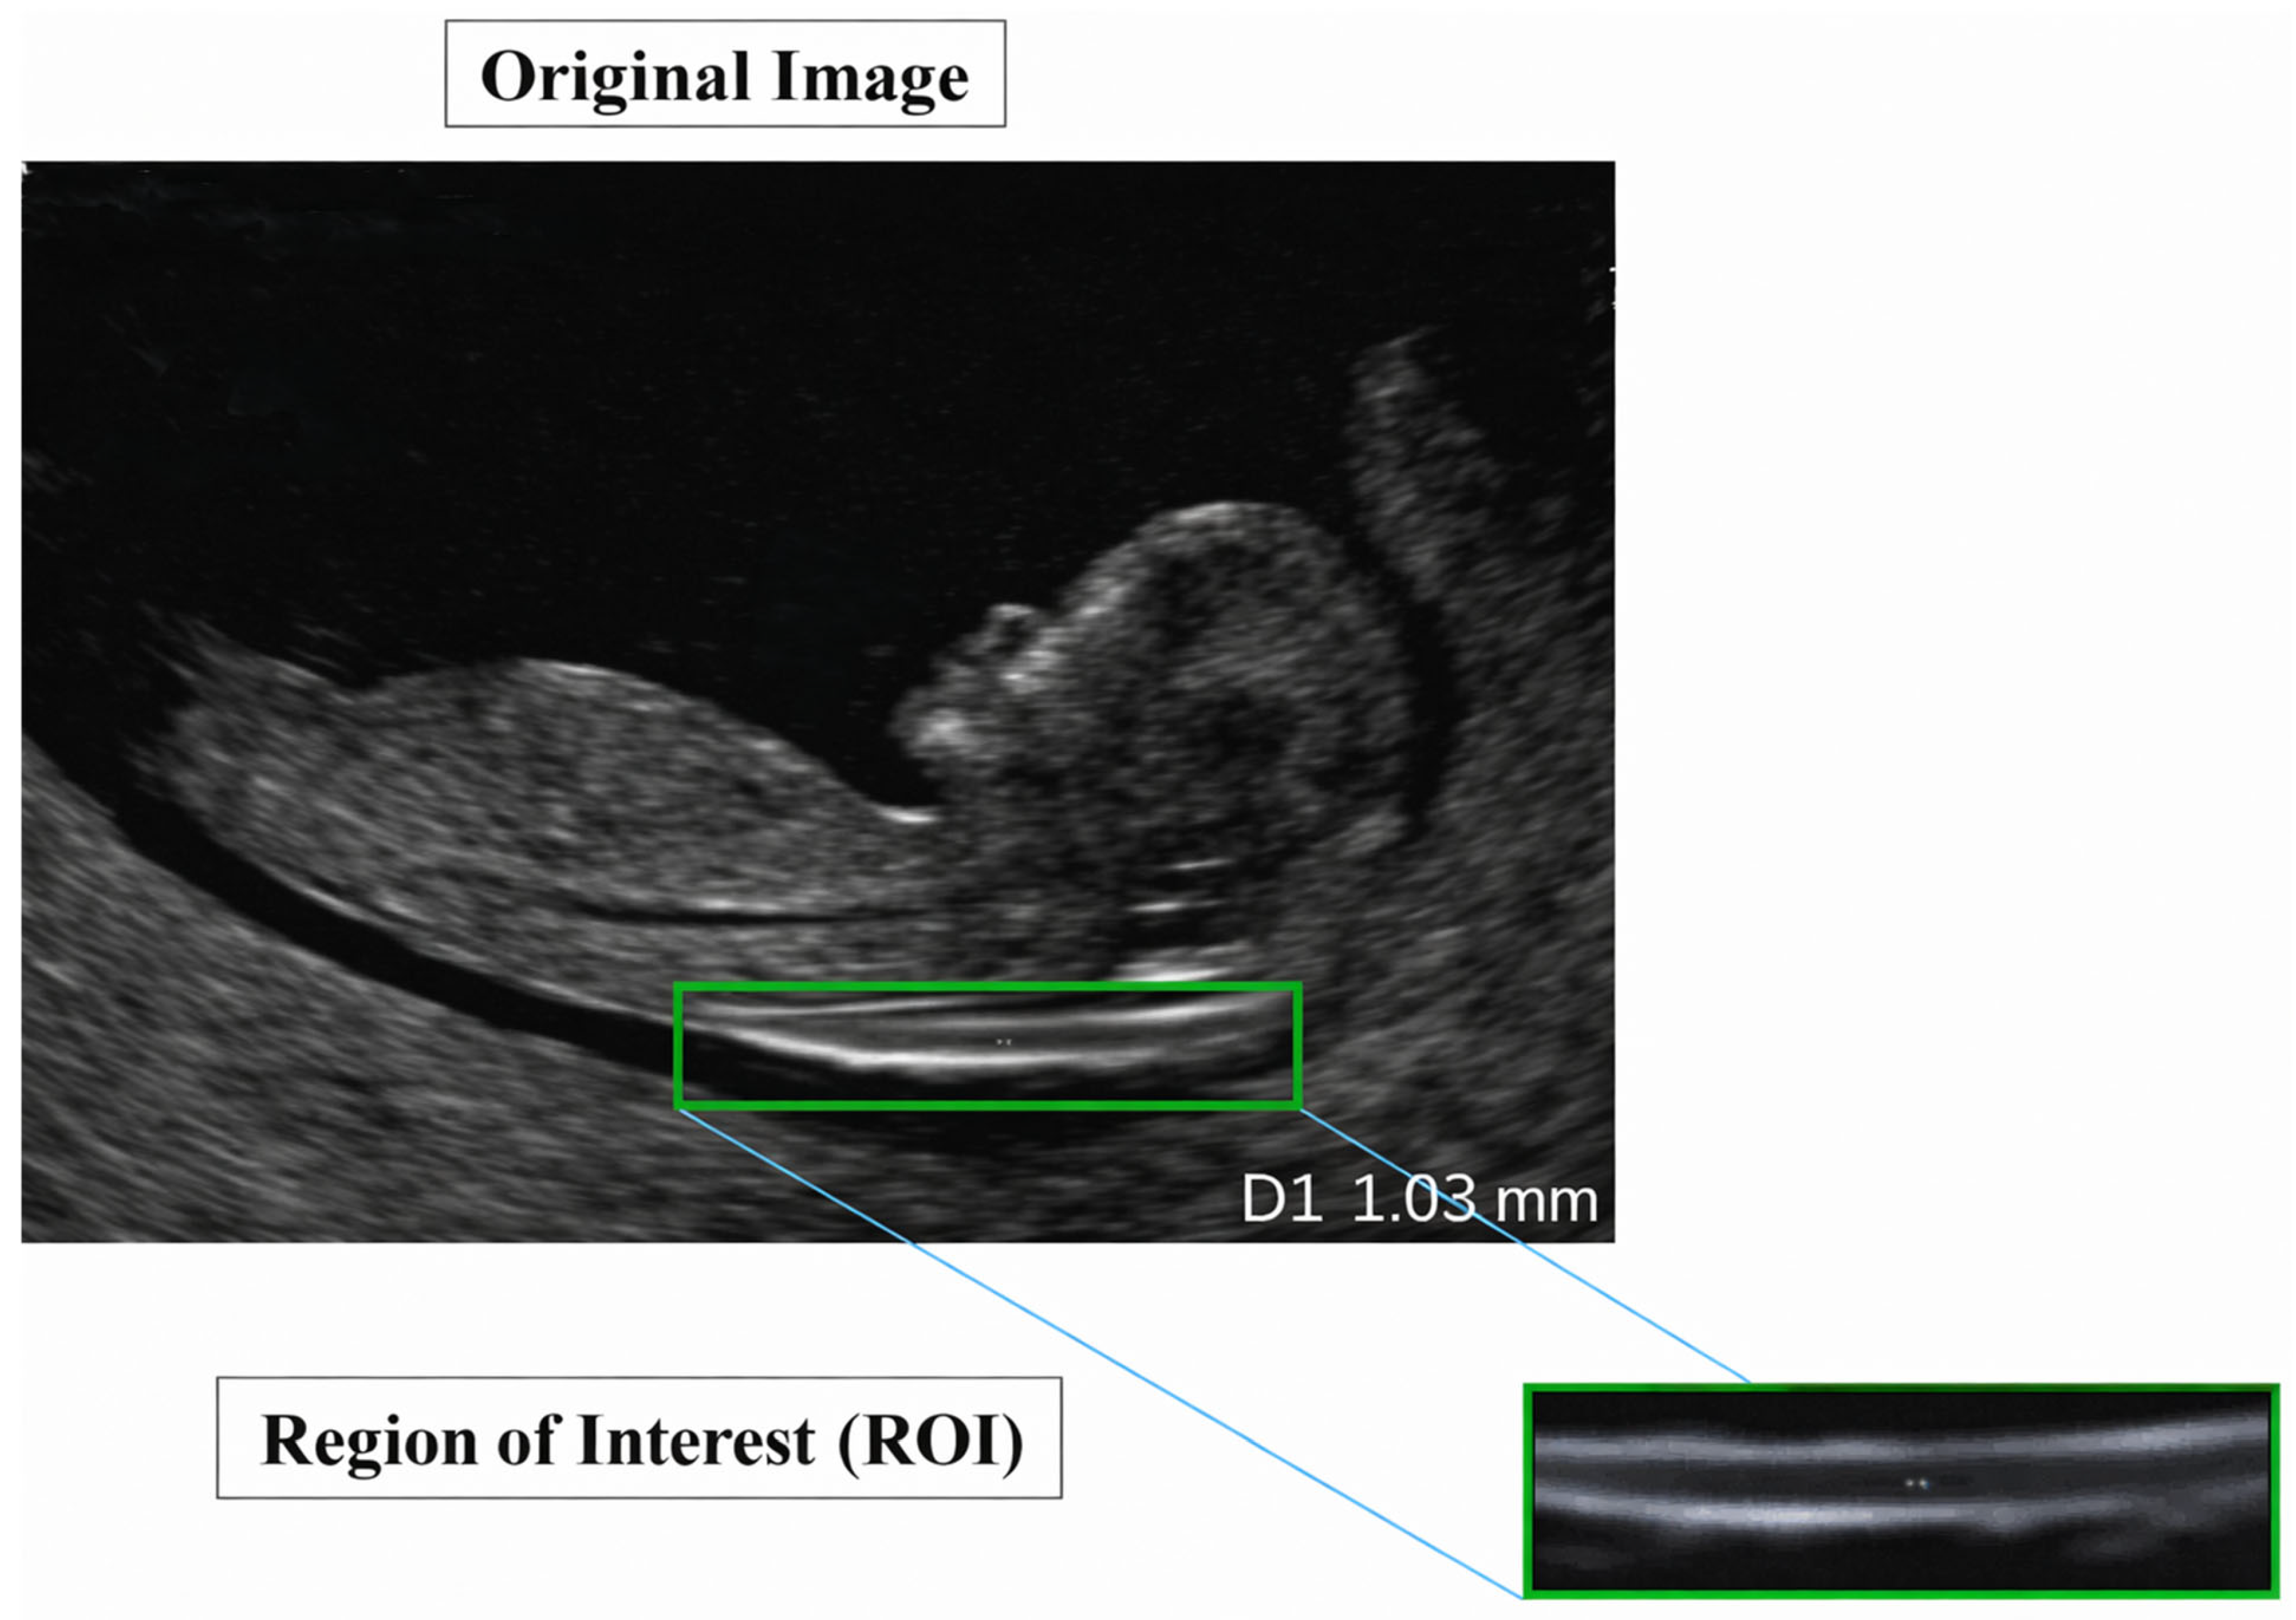

Nuchal Translucency (NT) screening, performed via ultrasound between 11 and 13 weeks + 6 days of gestation [2], is a cornerstone of first-trimester prenatal assessment and provides a critical, non-invasive marker for identifying fetuses at risk of chromosomal abnormalities, most notably Trisomy 21 (Down syndrome) [3]. NT is defined as the maximum thickness of the transient, subcutaneous fluid collection at the back of the fetal neck, as illustrated in Figure 2, and increased NT width particularly above 3.5 mm is strongly associated with elevated risks of aneuploidies and congenital heart defects [4].

Figure 2.

Nuchal translucency.

A representative example of a standard-view image from the NHOG dataset is presented in Figure 7.

Figure 7.

Sample image from the NHOG fetal ultrasound dataset.